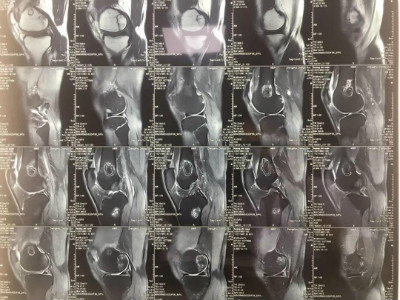

重要提示:如果反复膝关节疼痛,单纯按膝关节骨性关节炎治疗无效果。一定要建议患者进行膝关节磁共振检查,早做诊断。因为它很有可能由于患者的不重视发展成为骨坏死。即股骨下段,胫骨上段骨坏死。

同时也提醒广大的患者朋友,反复难愈的膝关节疼痛还有一种可能就是骨梗死,它也属于坏死的一种,只是坏死的部位以股骨下段,胫骨上段为主。同样也是只有做膝关节磁共振才可以分辨出来。